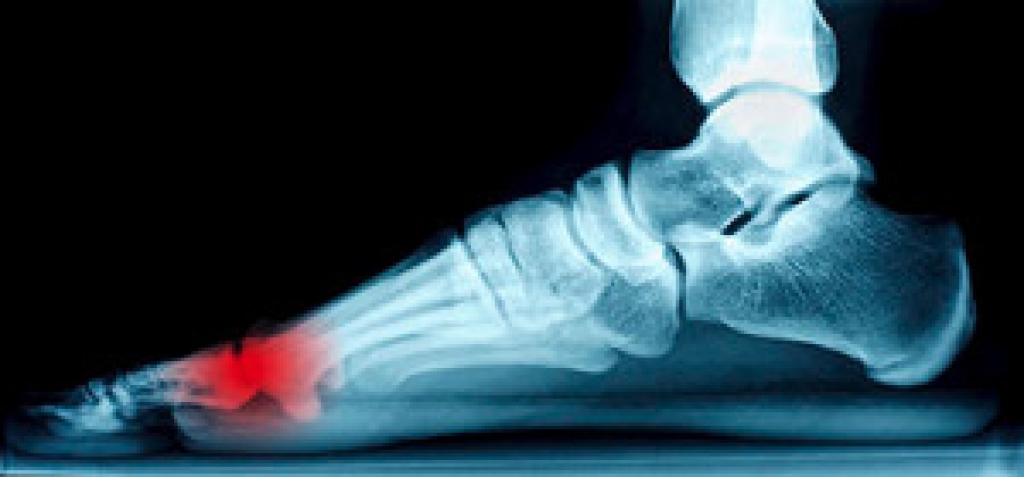

- Plantar fasciitis is another foot condition that can be caused by obesity. Plantar fasciitis is an inflammation of the tissue along the bottom of the foot, which causes pain and stiffness while walking and climbing stairs.